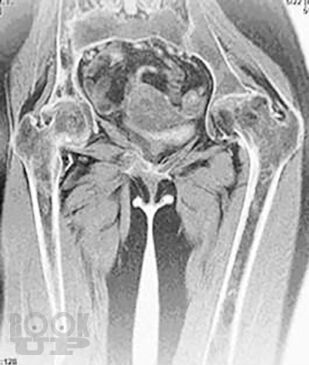

Болезнь Гоше относится к системным заболеваниям неопухолевой природы, в основе которых лежат наследственные дефекты метаболизма, приводящие к накоплению в органах и тканях нерасщепленных продуктов нормального обмена веществ. В случае болезни Гоше дефектом метаболизма является дефицит фермента, ответственного за метаболизм липидов.

Цель книги — познакомить врачей различных специальностей с основными клиническими проявлениями болезни Гоше, продемонстрировать исключительную вариабельность течения болезни на примере конкретных клинических случаев, показать характерные ошибки диагностики и ведения пациентов с болезнью Гоше. Помимо врачей, книга может быть полезной для образования самих пациентов и их родственников, так как некоторые особенности клинического течения заболевания напрямую связаны с социально-бытовыми аспектами: образом жизни, физической активностью, наличием бытовых интоксикаций и др.